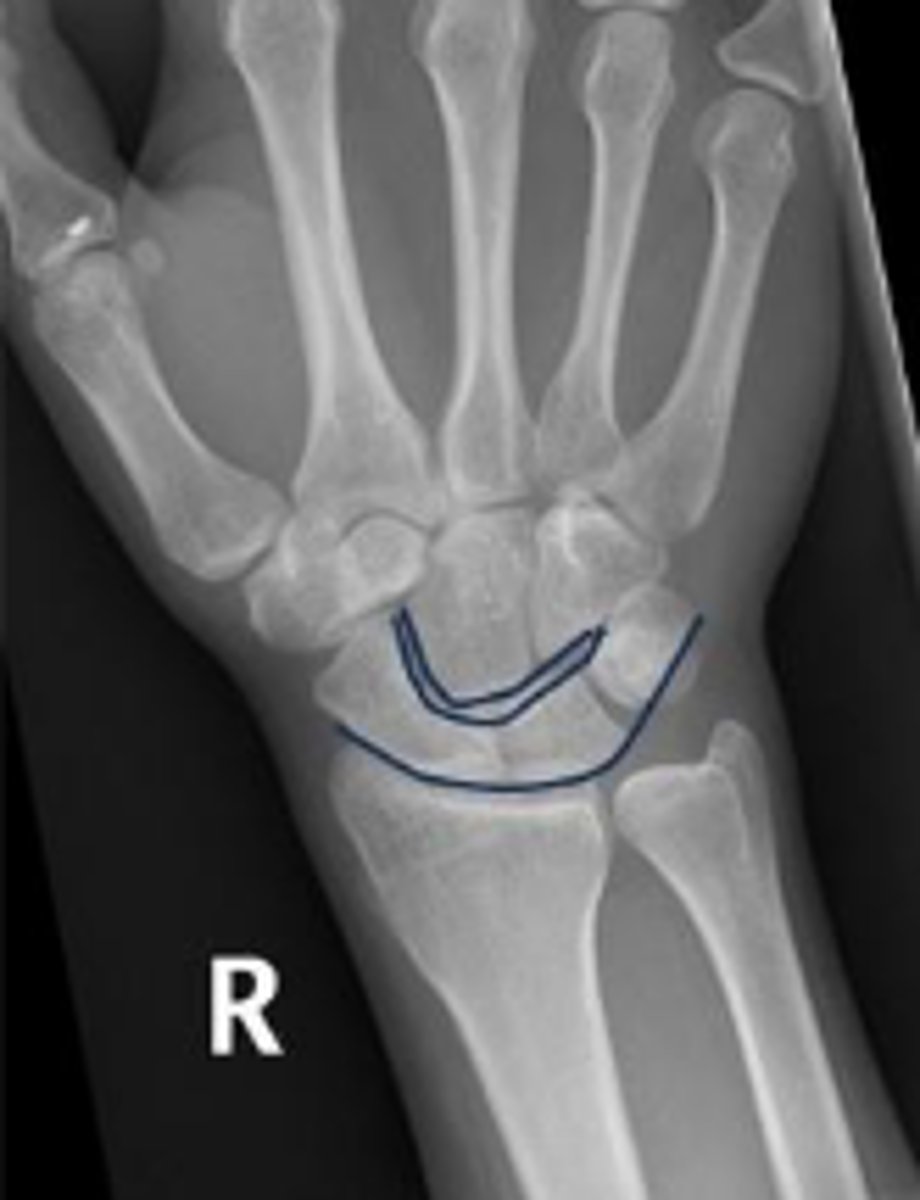

3 arcs of carpal alignment

What is the name of the assessment

Proximal cortical aspect of the first (proximal)

carpal row (ARC 1)

What are the landmarks for the most proximal line in the assessment?

Distal cortical aspect of the first (proximal) carpal

row (ARC 2)

What are the landmarks for the most middle line in the assessment?

Proximal cortical aspect of the second (distal)

carpal row (ARC 3)

What are the landmarks for the most distal line in the assessment?

SLAC wrist; carpal dislocation, carpal fracture

Name 2 conditions that will result in an alteration of the assessment?